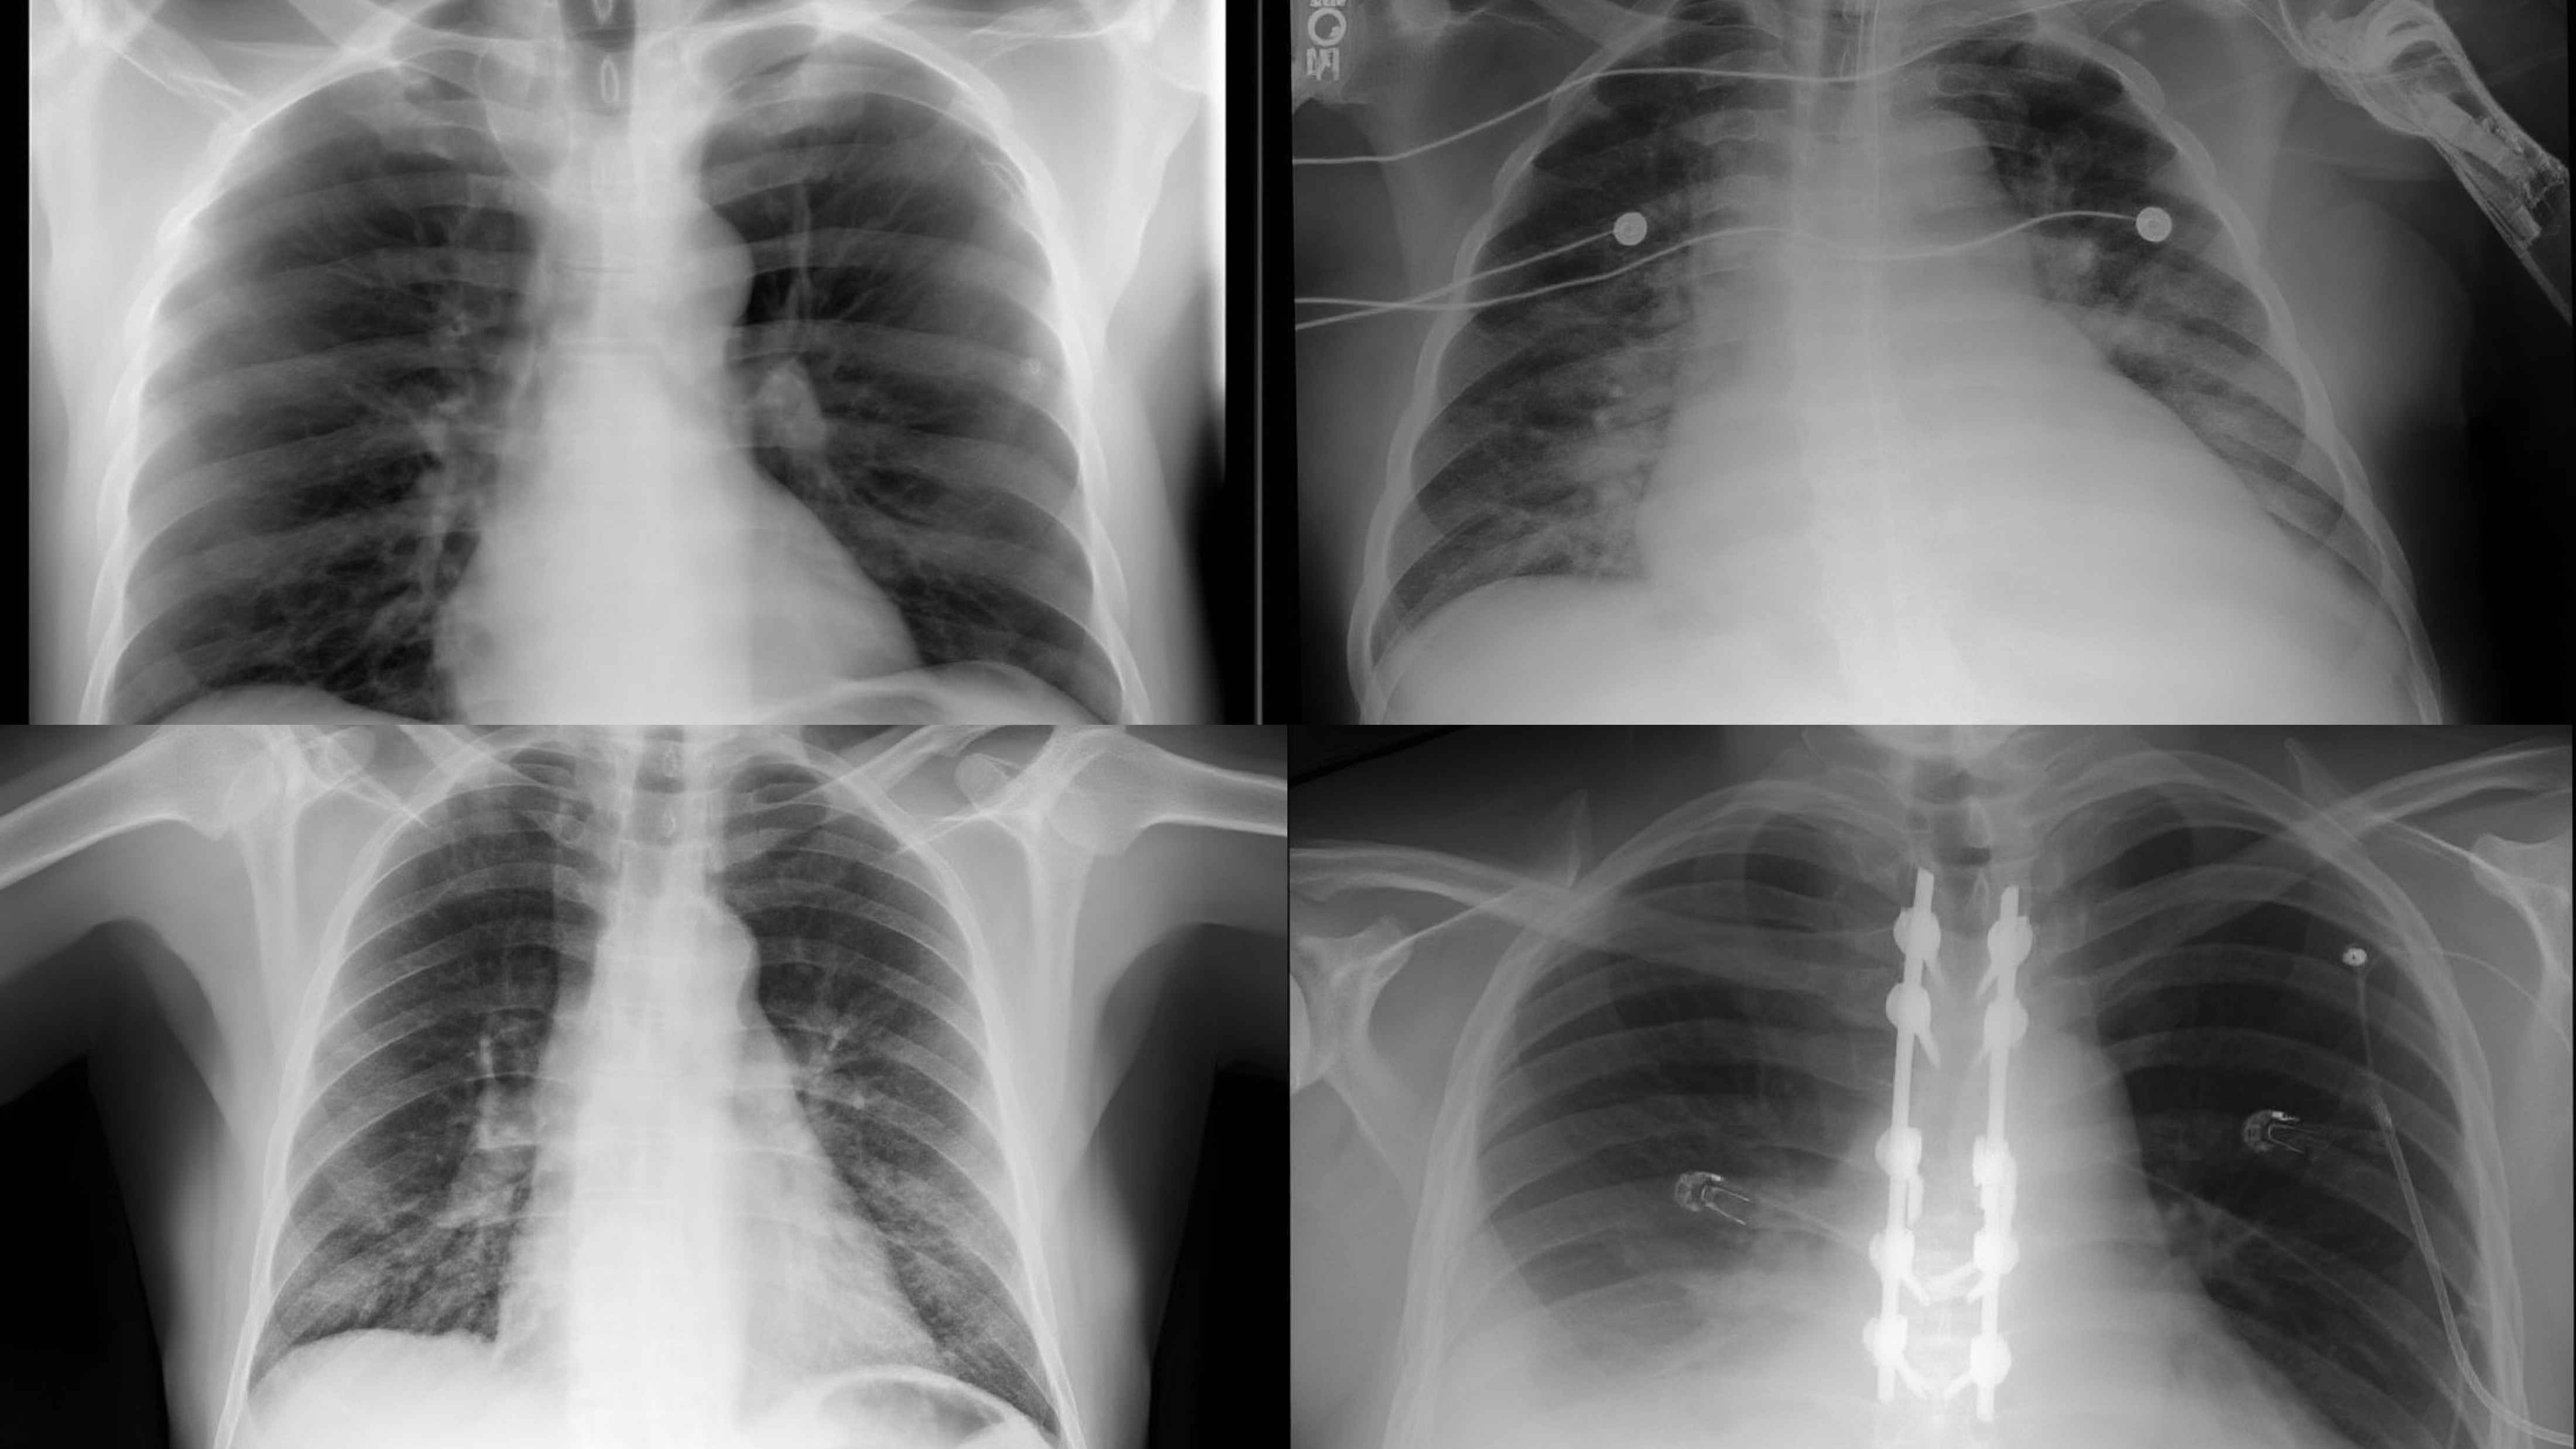

Chest X-ray

Chest X-ray (CXR)

CT Scan